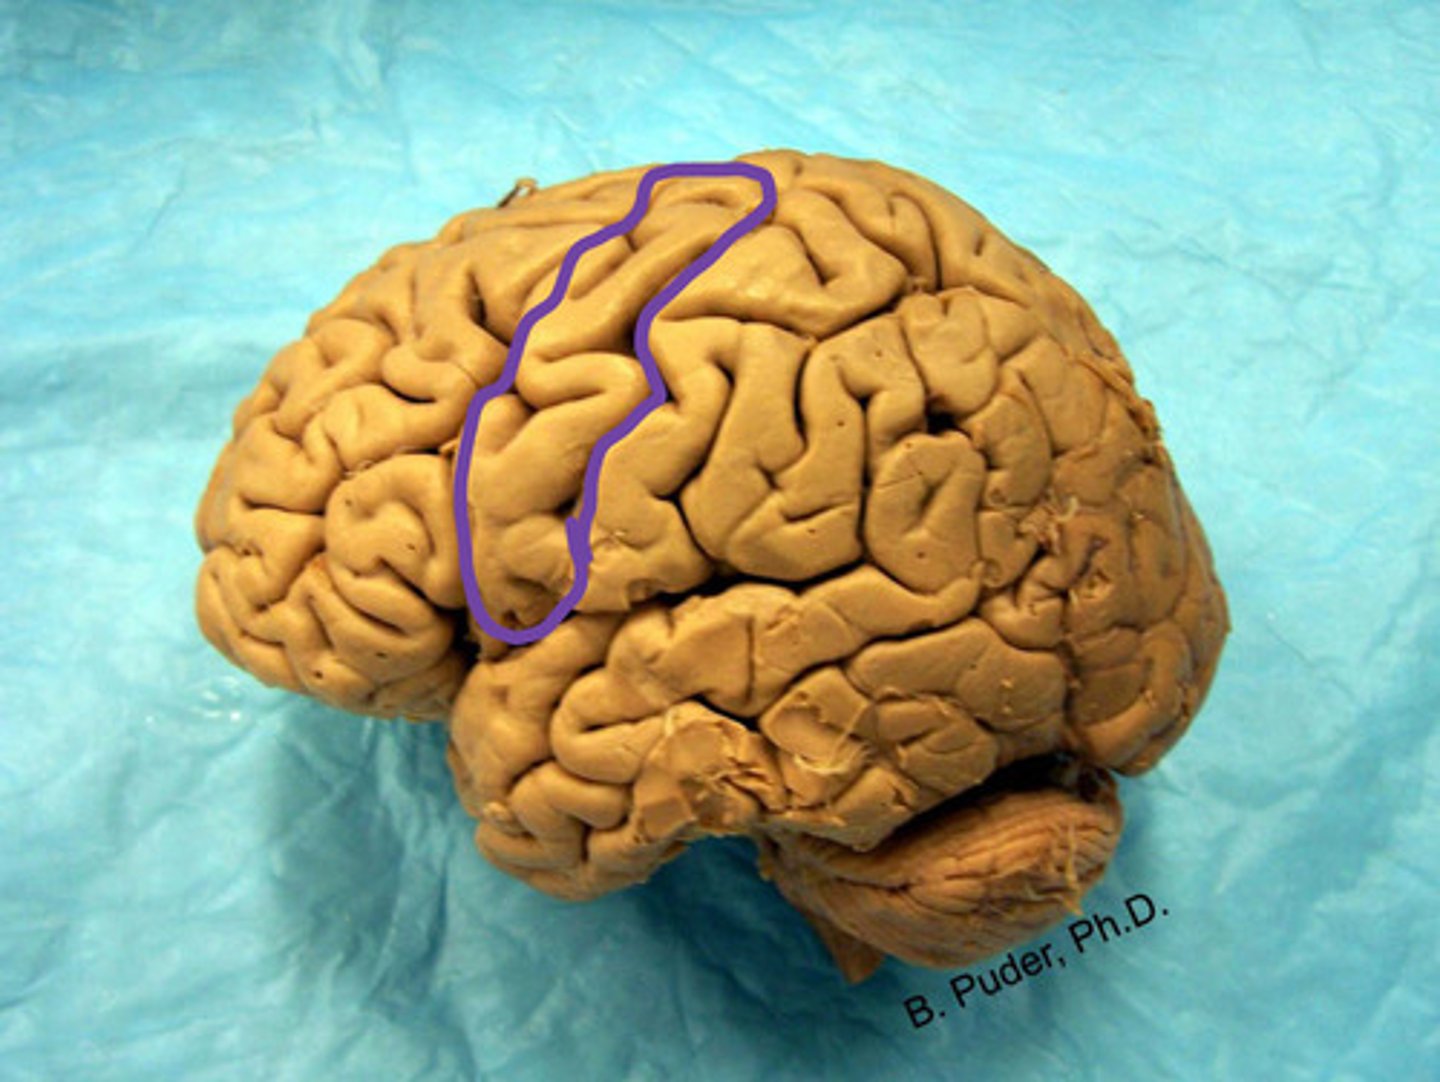

pre-central gyrus

label

precentral gyrus

Which brain area is motor control to the contralateral from head to hip?

postcentral gyrus

Which brain area is somatosensation control to the contralateral from head to hip?